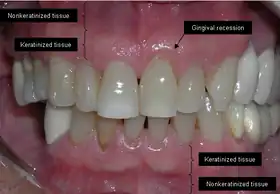

The soft tissue in the oral cavity is classified as either keratinized or nonkeratinized based on the presence of keratin in the epithelium.[4] In health, the soft tissue immediately around the teeth is keratinized and is referred to as keratinized tissue or gingiva. Alveolar mucosa is non keratinized oral epithelium and is located apical to the keratinized tissue, delineated by the mucogingival junction (MGJ). It should also be pointed out that mucosa can surround a tooth in health.[5] Nonkeratinized tissue also lines the cheeks (buccal mucosa), underside of the tongue and floor of the mouth. The lips contain both non-keratinized tissue (on the inside) and keratinized tissue on the outside, demarcated by the vermillion border. The dorsum of the tongue is keratinized and features many papillae, some of which contain taste buds.[6]

Exposure of the tooth root due to loss of keratinized tissue around the neck of a tooth is referred to as gingival recession. This can result in sensitivity or pain from the exposed tooth root surface (dentin is more permeable and soft compared to enamel and dentin is what makes up the tooth root).[7] Recession may also cause an unasthetic appearance especially if located in the anterior dentition (front teeth). While not all cases of gingival recession require surgical correction, there are various options if that is what the patient desires.[8] It should be reinforced that recession left untreated will not result in tooth loss, contrary to popular belief. Also, recession that is left untreated can be maintained and the inflammation kept at bay with proper brushing and oral hygiene technique.[5] On the other hand, if one desires to pursue corrective therapy, there are a wide variety of techniques ranging from autograft (your own tissue, usually taken from the palate), allograft (someone else's tissue, cadaver), xenograft (animal, usually porcine or bovine) or simply repositioning of the tissue native to the site.[9] The benefits of corrective therapy often result in decreased sensitivity through coverage of the root surface in addition to a gain in the keratinized tissue mentioned beforehand.